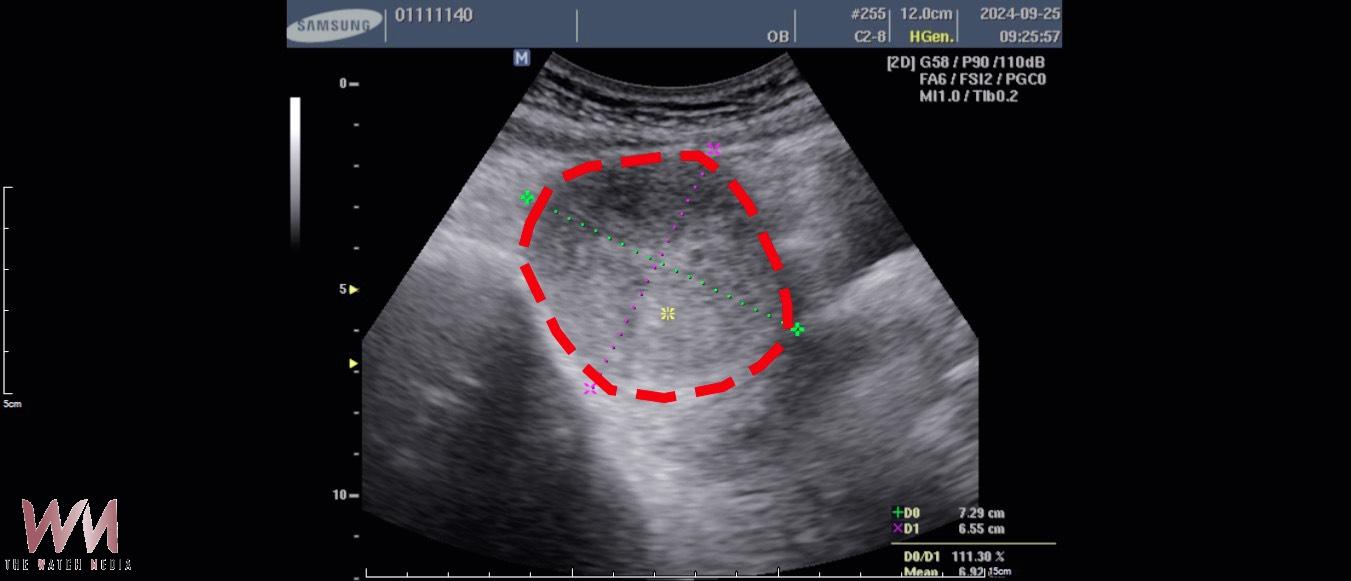

手術前:7.3×6.5×6.2公分。(圖/林新醫院提供)

(觀傳媒中彰投新聞)【記者廖妙茜/台中報導】52歲的徐女士,長年飽受經痛、頻尿及下腹悶脹等症狀困擾。於113年9月20日至林新醫院健檢中心接受檢查時,經婦產科超音波檢查發現,其子宮前壁長有一顆約 7.3×6.5×6.2 公分、體積達 294 立方公分 的子宮肌瘤,大小約等同一顆中型芒果,且已壓迫膀胱,導致其日常需頻繁如廁、夜間多次起床影響睡眠,外出時亦須時時留意洗手間位置,生活品質明顯受到影響。